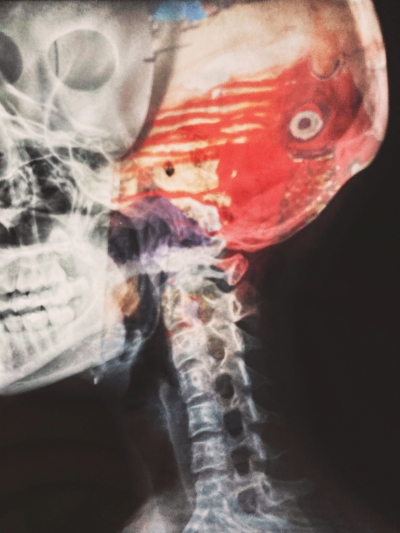

우리나라에서 단일 질환으로 사망률 1위는 뇌졸중이라고 하는데요. 뇌졸중은 뇌의 혈관이 좁아지면서 혈관이 막히며 발생하는 질환입니다.

고혈압이나 당뇨 같은 위험인자를 지닌 사람은 더욱 위험하며 술, 담배, 짠 음식, 기름진 음식 등 혈관 건강을 망치는 음식이나 습관들도 뇌졸중 위험을 높이는 인자 중에 하나입니다.

뇌졸중은 초기에 치료하면 그만큼 예후도 좋습니다. 뇌졸중 전조증상에 대해 알아보고 미리 건강을 챙기면 좋을 것 같습니다.